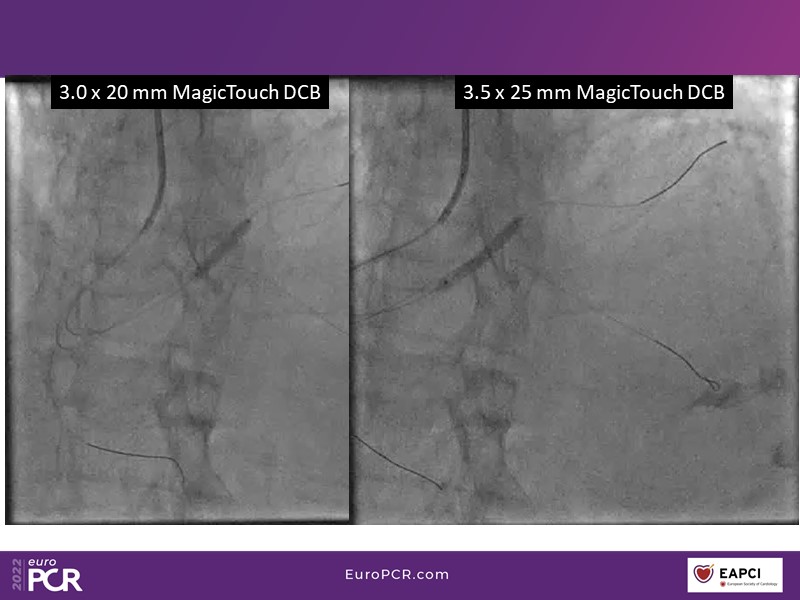

- To find out more about the application and mechanism of a sirolimus coated balloon for coronary artery disease treatment with case presentations in complex settings